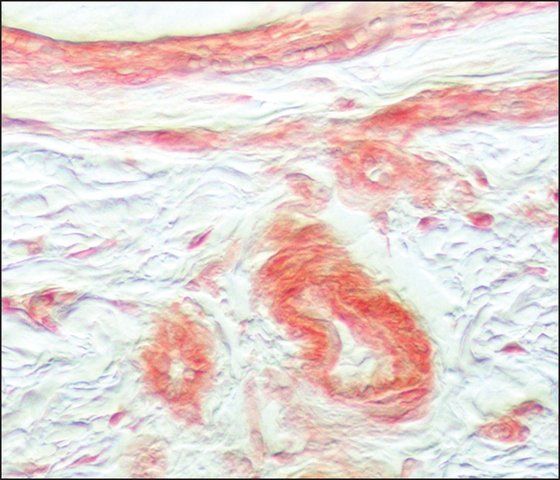

Fibroblast growth factor receptor 1 (FGFR-1) belongs to the family of FGFRs. At the mRNA level, FGFR-1 is highly expressed in developing human tissues including the brain (preferentially in neurons), vascular basement membranes, skin, and bone growth plates.

Anti-FGFR-1 antibody is specific for human FGFR-1 and does not react with human FGFR-2 and FGFR-3. The immunizing peptide specifically inhibits the staining of anti-FGFR-1 antibody.

| technique(s) | immunohistochemistry (formalin-fixed, paraffin-embedded sections): 1:200 using trypsin-digested human and animal tissue sections immunoprecipitation (IP): suitable western blot: 1:400 using an extract of FGFR-1 transfected cells |